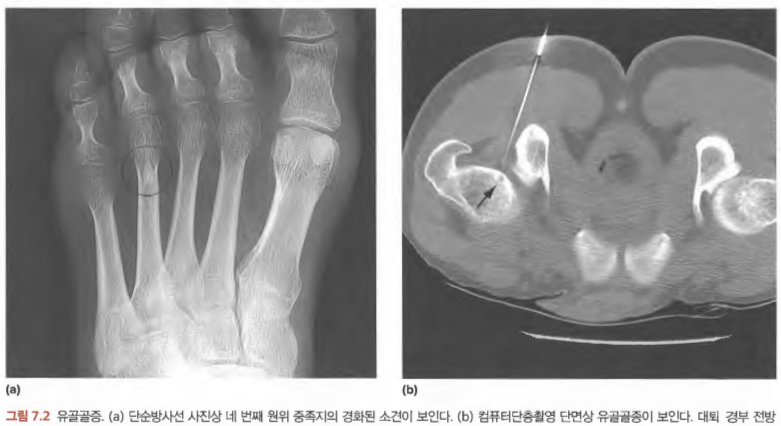

- Osteoid osteoma: 운동으로 유발되는 통증, 아스피린으로 호전되는 야간통, Central nidus.